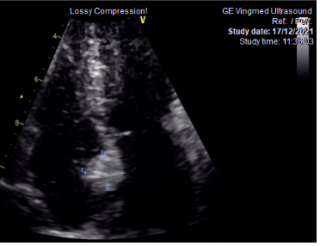

Γενικά, το διαθωρακικό υπερηχογράφημα (ακολουθείται σε μερικές περιπτώσεις από το διοισοφάγειο) είναι η πρώτη διαγνωστική εξέταση. Οι καρδιακοί όγκοι μπορεί να είναι ενδοκοιλοτικοί ή ενδομυοκαρδιακοί (ενδοτοιχωματικοί). Η ηχοκαρδιογραφία απεικονίζει τους ενδοκοιλοτικούς όγκους ως μία πυκνή υπερηχογενή μάζα ακίνητη με ευρεία βάση ή κινητή με μίσχο, που είναι προσαρτημένη στο ενδοκάρδιο. Αντίθετα, οι ενδοτοιχωματικοί όγκοι εμφανίζονται ως μία τοπική πάχυνση του μυοκαρδιακού τοιχώματος μίας κοιλίας. Οι καρδιακοί όγκοι μπορεί επίσης να προβάλλουν το περικάρδιο, με ή χωρίς συνύπαρξη περικαρδιακής συλλογής.

Στην ηχοκαρδιογραφία, το μύξωμα έχει την εμφάνιση μίας ανομοιογενούς κινητής μάζας, συχνά περίπου σφαιρικής, διαμέτρου συνήθως 4-8 cm, με λεία ή με λοβωτή (που φέρει μικρά τόξα στο περίγραμμά της) επιφάνεια. Η μάζα είναι προσαρτημένη στην ενδοκαρδιακή επιφάνεια (συνήθως στο μεσοκολπικό διάφραγμα) με στενή βάση, δηλαδή μίσχο. Σε κάποιες περιπτώσεις μπορεί να συνδέεται στο μεσοκολπικό διάφραγμα με ευρεία βάση. Η ηχογένεια τους δεν είναι ομοιογενής και μπορεί να περιλαμβάνουν υπόηχες περιοχές και σε κάποιες περιπτώσεις ασβεστώσεις. Τα πολυποειδή μυξώματα είναι μεγαλύτερα με λεία επιφάνεια και περιλαμβάνουν υπόηχες και κυστικές περιοχές λόγω εστιών αιμορραγίας και νέκρωσης εντός του όγκου . Τα θηλοειδή μυξώματα τείνουν να είναι μικρότερα και έχουν πολλαπλές λαχνοειδείς προσεκβολές. Αυτός ο υποτύπος σχετίζεται με εμβολικά φαινόμενα. Η θεραπεία ενός καρδιακού μυξώματος είναι η ριζική (πλήρης) χειρουργική αφαίρεση του όγκου.